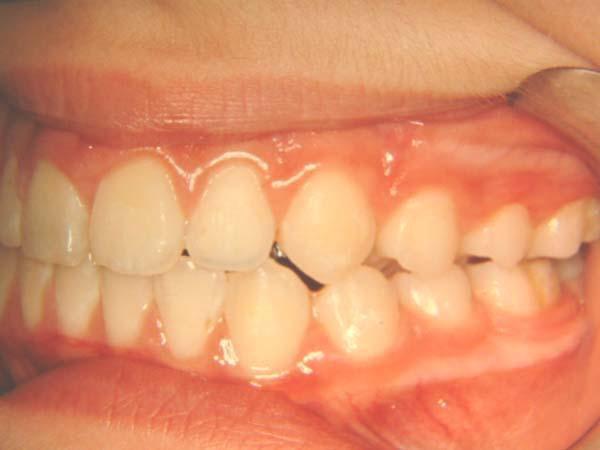

1η περίπτωση

Αρχική οδοντοσκελετική κατάσταση παιδιού με προγναθισμό άνω γνάθου και έντονη οριζόντια πρόταξη άνω τομέων Η σημασία της στοματικής υγιεινής και ορθοδοντικής

026

πρόληψης

027 Αμέσως μετά το τέλος της ορθοδοντικής θεραπείας. Οι αλλαγές στην οδοντική του σύγκλειση αλλά και στο πρόσωπο είναι εμφανείς 15 χρόνια μετά την αρχική περάτωση της θεραπείας, το αποτέλεσμα παραμένει σταθερό και ο ασθενής απέκτησε ένα υγιές και αρμονικό χαμόγελο και πρόσωπο. Η σημασία της στοματικής υγιεινής και ορθοδοντικής πρόληψης